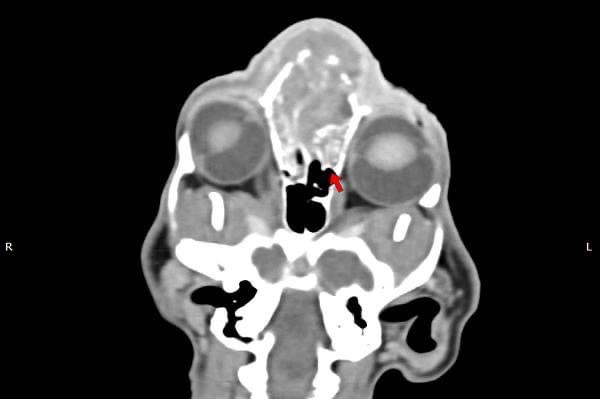

貓咪 鼻腔腫瘤腺癌 Adenocarcinoma

鼻腔腫瘤的診斷需要仰賴電腦斷層掃瞄定位病灶處,同時使用鼻腔內視鏡探查、採樣才能確診,同時有這兩項設備的醫院並不多,所以臨床事並不是那麼容易確診。貓咪幾個月前開始打噴嚏、流鼻、鼻塞越來越嚴重,他院住院治療改善不佳後轉診至築心檢查。

鼻腔腫瘤的診斷需要仰賴電腦斷層掃瞄定位病灶處,同時使用鼻腔內視鏡探查、採樣才能確診,同時有這兩項設備的醫院並不多,所以臨床上並不是那麼容易確診。狗狗的慢性鼻炎維持3-4個月,越來越嚴重,他院轉診至築心,經由內視鏡+電腦斷層確認為鼻腔上皮癌,而且由於病程時間長,已經轉移至胸腔,代表壽命不長了,至少家人心中有個答案,有心理準備陪狗狗最後一段路。

狗狗 鼻腔腫瘤 淋巴癌

鼻腔腫瘤的診斷需要仰賴電腦斷層掃瞄定位病灶處,同時使用鼻腔內視鏡探查、採樣才能確診,同時有這兩項設備的醫院並不多,所以臨床事並不是那麼容易確診。狗狗如果有打噴嚏、鼻分泌物 鼻塞,對藥物治療反應不好, 就還是要做進一步檢查才會比較安心唷!

鼻上皮細胞癌

鼻腔症狀是門診中狗貓最常見的主訴之一,但在診斷上卻不那麼容易,在缺乏如電腦斷層、內視鏡、牙科X光等特定設備的情況下,門診醫師多只能嘗試性的給藥觀察,對於慢性、頑固、難治的鼻腔問題往往便束手無策了。

柴犬皮皮因長期有鼻塞、流鼻血、流鼻水的症狀來築心就診,在這之前已經換過兩間醫院,但治療效果都不太好。在一系列的評估後,我們為皮皮安排了電腦斷層以及鼻腔內視鏡的檢查,檢查後發現在皮皮的鼻腔內有疑似腫瘤的團塊,並且向後侵入鼻竇,甚至已經接近大腦。我們運用內視鏡設備採樣取得了團塊的切片,並得到鼻上皮細胞癌的診斷。